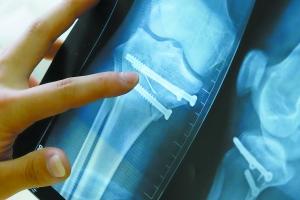

从吕先生右膝的X光片可以看到一根细针深入其中。记者苏俊杰 实习生何加劼摄

手术做完了,探针却断裂留在了骨头里!在白云石井人民医院住院的吕先生就经历了这一遭,X光片上那根长长的探针历历在目,他很担心骨内的探针对以后行走会带来影响。

“当时可能麻药还没有过,我自己也没有觉得疼?!甭老壬担约夯故呛艿P?,不过李医生告诉他,没有事,不到万分之一的情况会有影响。如今,大半年过去了,吕先生右膝盖的部位还在肿胀。他表示这几个月他基本上躺在床上,偶尔拄着拐杖下床走一走,但是发现右腿完全使不上力。前几天,他的右腿被拍了X光片,让他吃惊的是,X光片上显示那根留在他骨内的针有约5厘米长?!肮植坏梦业挠蚁ジ枪苏饷淳枚济挥邢祝胰衔馐且缴氖韬龅贾鲁こさ奶秸胍帕粼谖业墓峭防??!甭老壬?。